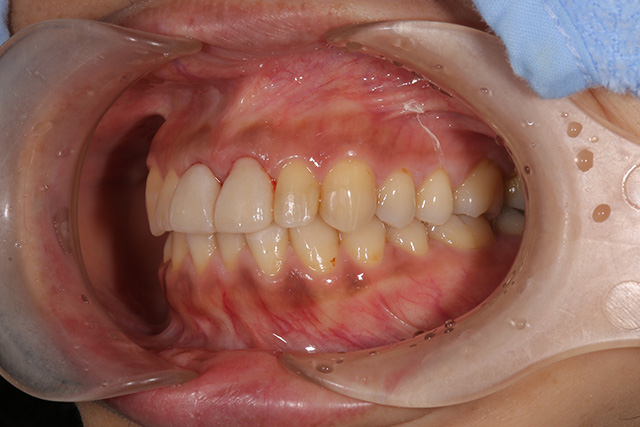

審美症例